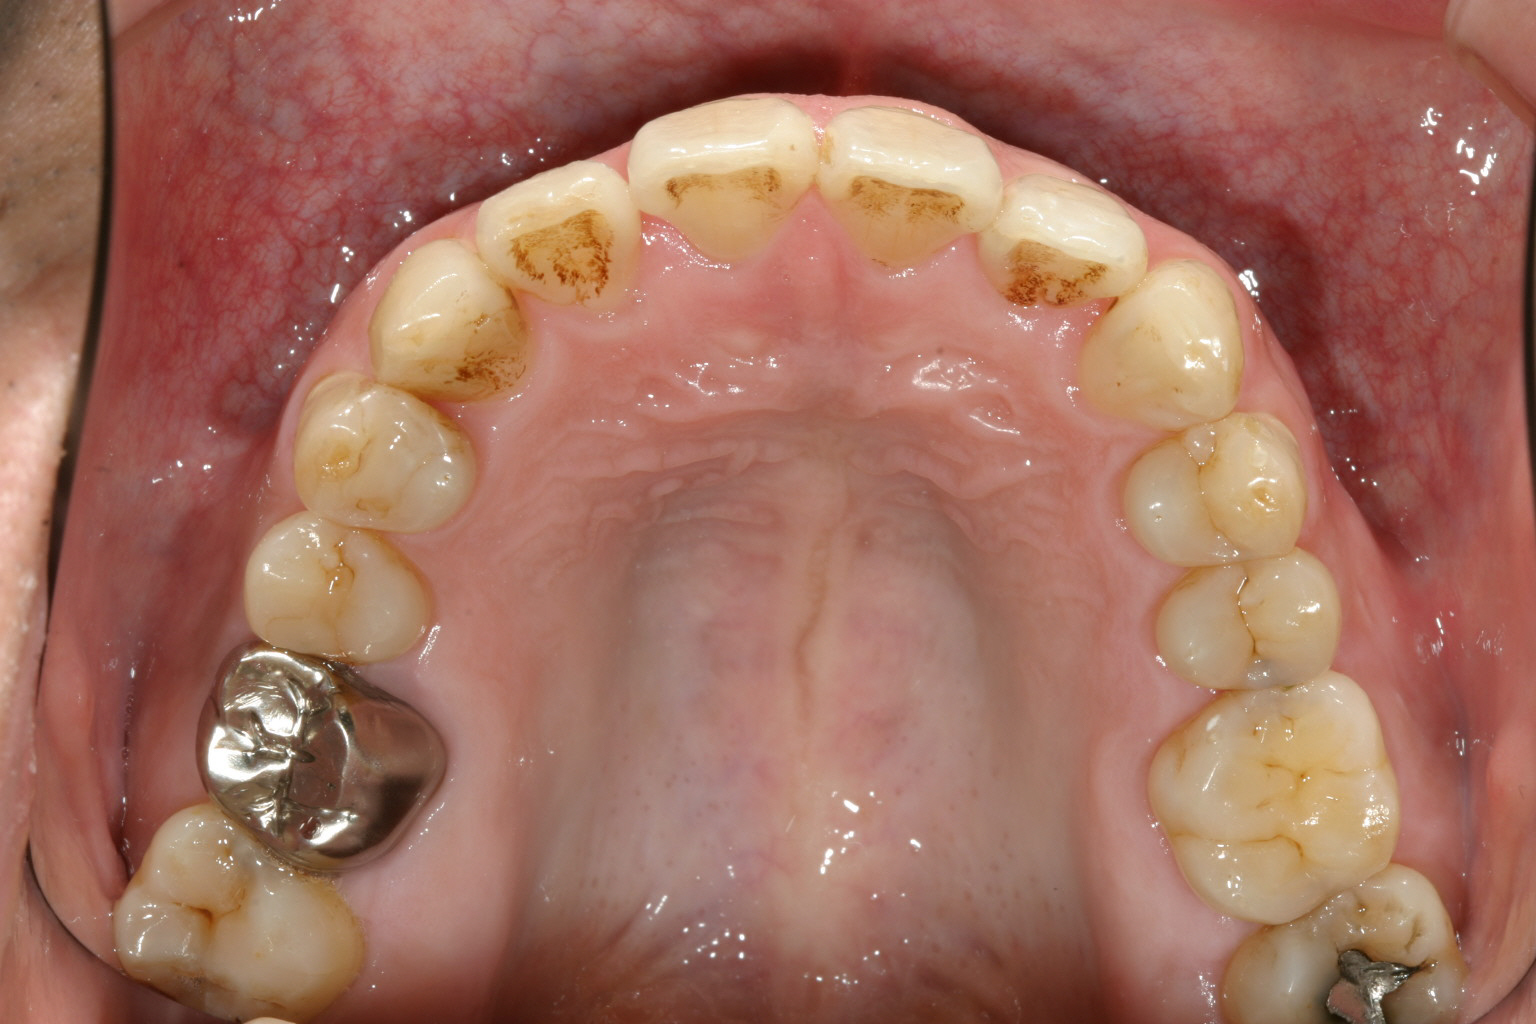

アーチを拡大し綺麗に整列しました。